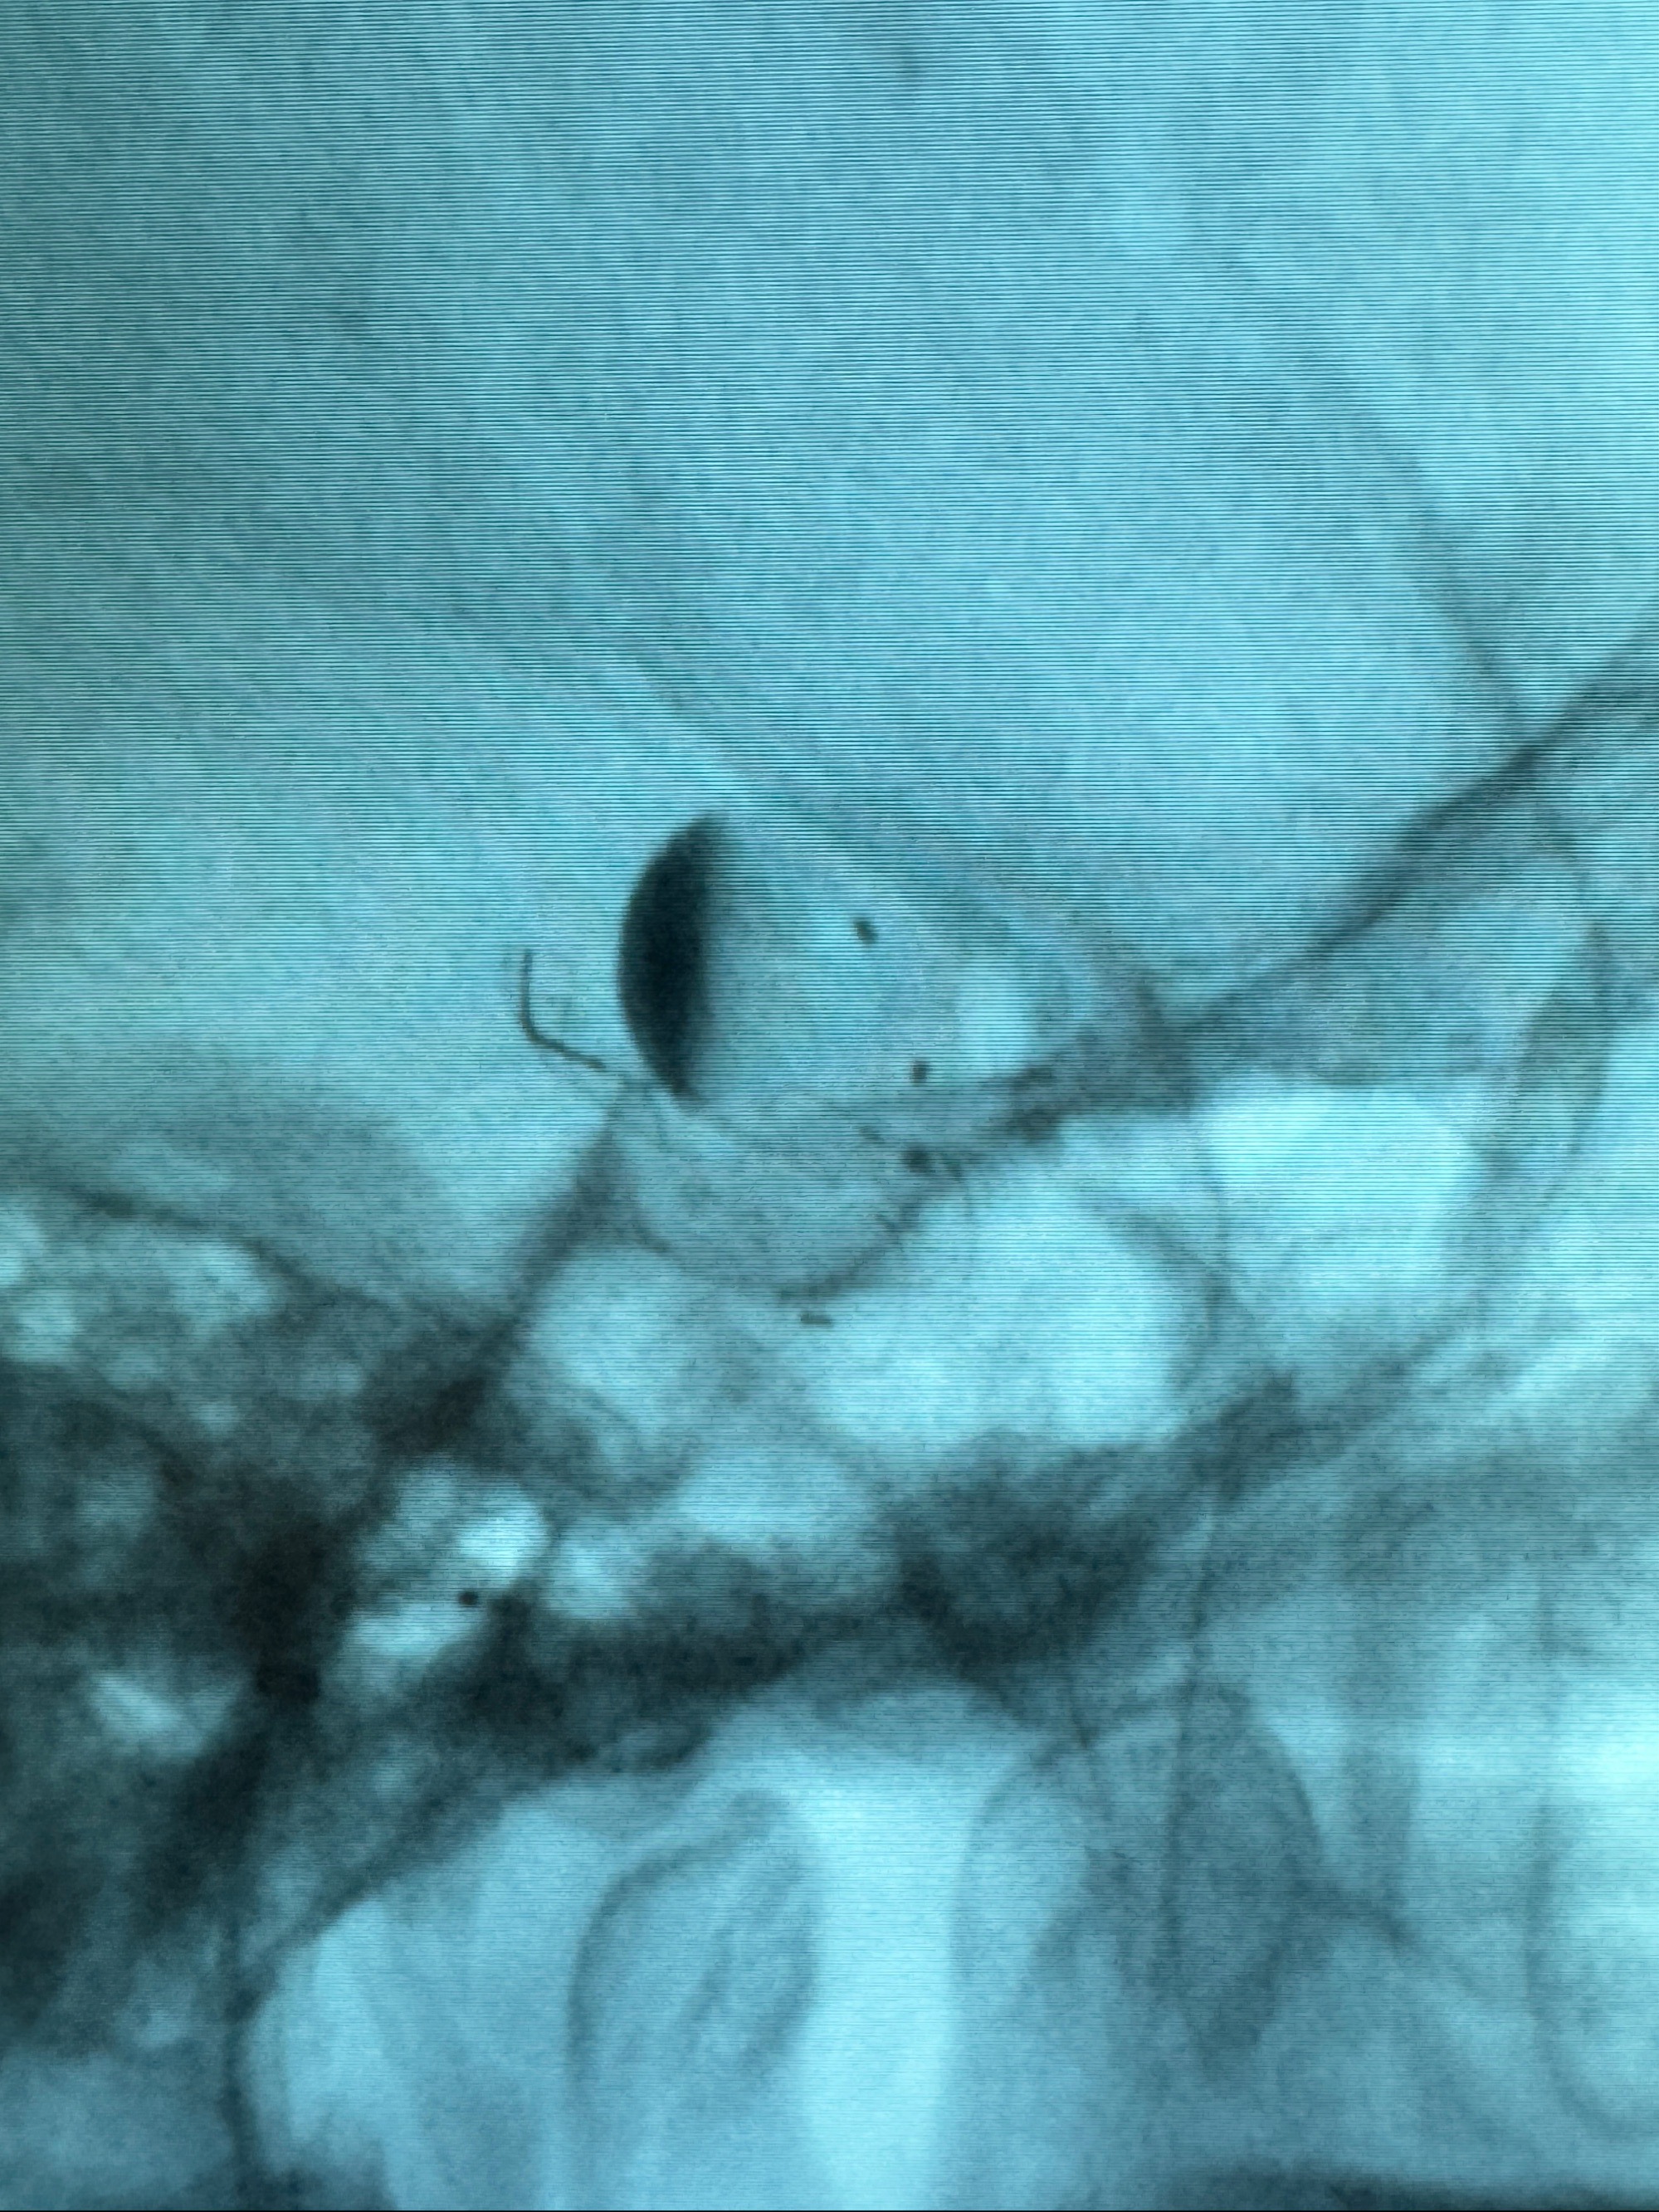

透视可见红圈部分为支架导管的头端

手推冒烟显示支架位置及展开情况,箭头为支架导管的位置

尝试回收支架失败,只能考虑释放支架了

逐帧图像展示歪着脖子释放支架,旁边吩咐助手手机摄影、拍照留像(透视机不能留影像)

看动脉瘤内造影剂滞留,未见明确射流,遂撤出预留的栓塞微导管,快速结束手术,经导引导管灌注替罗非班250ug。